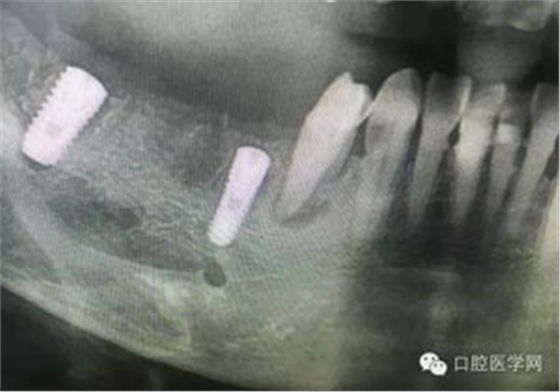

病例1:患者迫切希望保留自己的這一顆牙齒,根尖周陰影比較大,二度松動(dòng).而且旁邊有種植修復(fù)體,和患者溝通好后,治療好后觀察一個(gè)月后冠修復(fù),因?yàn)橛蟹N植的后期修復(fù),所以有了機(jī)會(huì)觀察,術(shù)后三個(gè)月和術(shù)后四個(gè)月,根尖恢復(fù)的還算不錯(cuò),希望能夠繼續(xù)觀察下去.這樣子的病例,做的時(shí)候我們一定要非常的小心,和患者要有充分的溝通以及不同科室的溝通然后決定怎么樣做比較好,假如就是出現(xiàn)了問題,到時(shí)候我們也比較好處理些,免得我們自己到時(shí)候不好收?qǐng)觥?/span> 病例2:364647中齲的樹脂充填,現(xiàn)在樹脂的充填材料非常之多,有些時(shí)候,我們感覺有了好的材料我們就可以做出好的修復(fù),可是這是在我們有扎實(shí)的基本功的基礎(chǔ)上的,我們可以沒有那么好的樹脂,那么多的顏色選擇,修復(fù)的那么的逼真,但是我們至少要恢復(fù)患者牙齒的功能,將腐質(zhì)去除干凈,薄壁弱尖消除掉,選擇好適應(yīng)癥,給患者以盡可能好的修復(fù)。 來源于KQ88